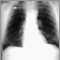

Pulmonary aspergilloma is a mass caused by a fungal infection that usually grows in lung cavities. It can also appear in the brain, kidney, or other organs.

Aspergillomas are formed when the fungus aspergillus grows in a clump in a lung cavity, or invades previously healthy tissue, causing an abscess.